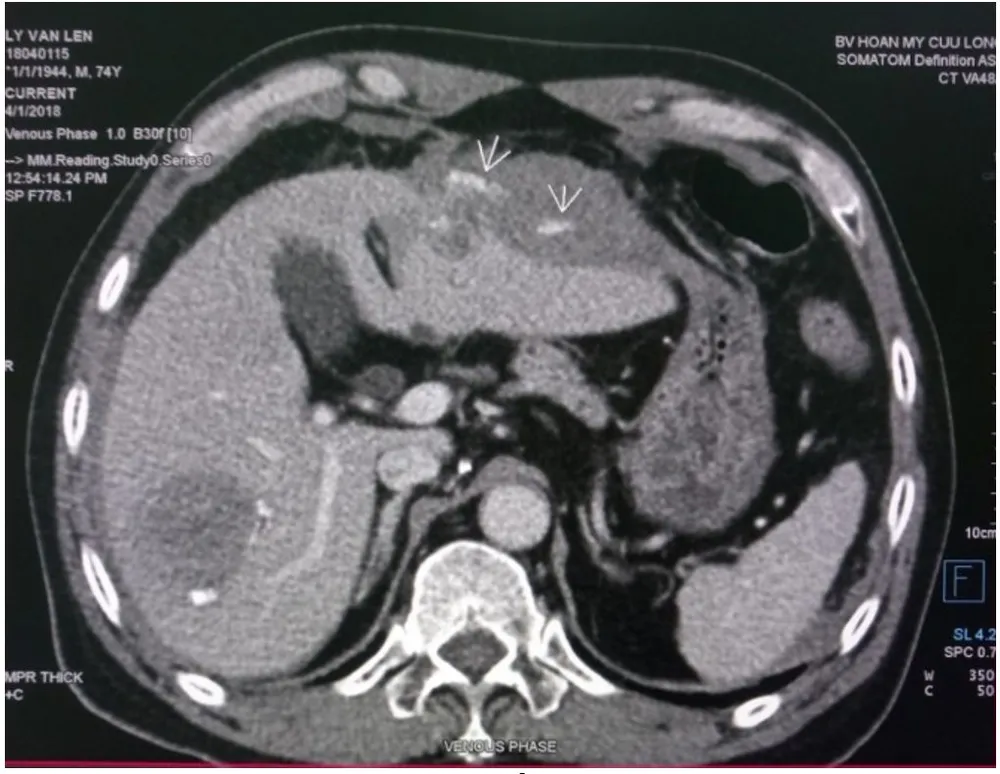

Cấp cứu thành công bệnh nhân bị vỡ khối u gan trái ảnh 1 Hình chụp cho thấy máu trong bụng bệnh nhân L.

Ngay lập tức các bác sĩ tiến hành xét nghiệm và kiểm tra các khâu cần thiết, các kết quả cận lâm sàng xác định nguyên nhân gây ra đau bụng cho bệnh nhân là do khối u gan trái bị vỡ, gây chảy máu trong bụng.